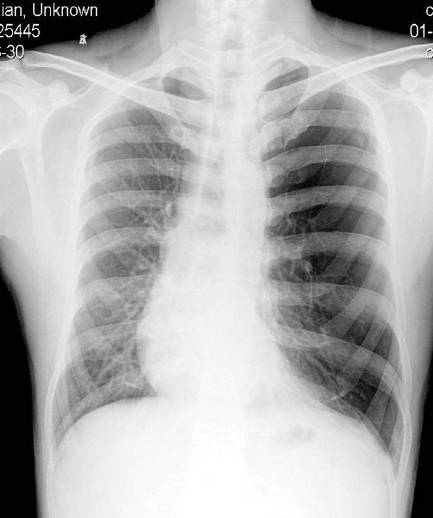

代偿性肺气肿属于局限性非阻塞性肺气肿,是由于一部分肺的纤维化或不张,或手术切除后,余肺膨胀代偿其胸腔内失去的体积所致。

代偿性肺气肿的范围和程度取决于肺部切除的多少或肺萎缩的情况。如果一侧肺完全切除或不张,对侧的肺可全部产生代偿性肺气肿,甚至形成纵隔疝。一叶、一段或少于一叶的代偿性肺气肿较为常见。由于其范围小,一般不产生明显的胸廓、横膈或心脏和纵隔的改变。